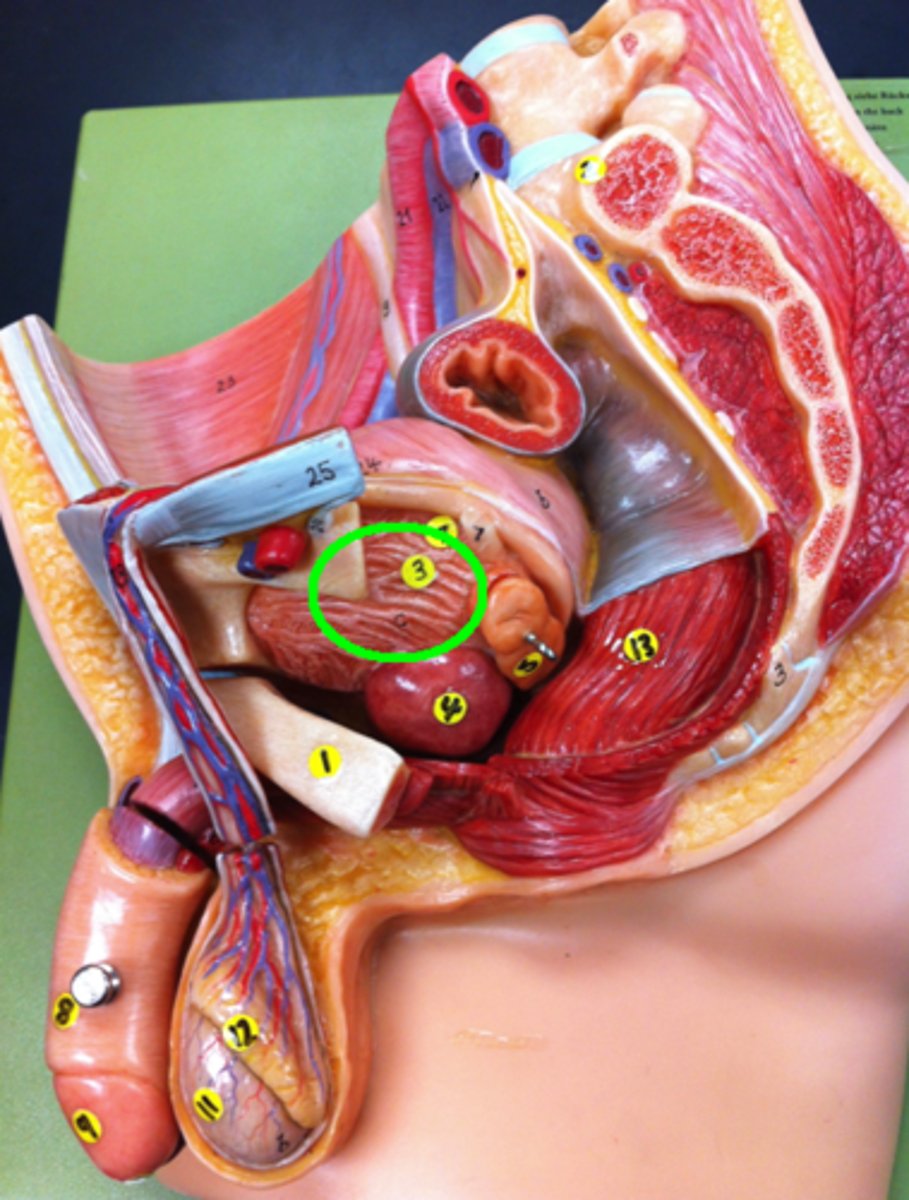

Prostate Gland

Corpora Cavernosum

Corpus Spongiosum

Ejaculatory Duct leading to the Prostatic Urethra